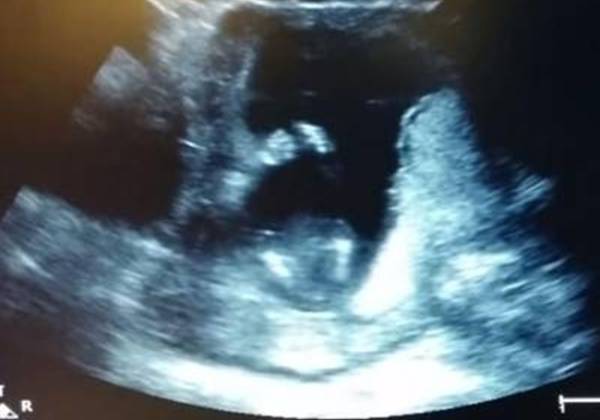

Las imágenes pertenecen a la ecografía que un ginecólogo le hizo a una mujer embarazada de 14 semanas. Para sorpresa de todos, marido incluido, el bebé aparece dando palmas hasta en tres ocasiones mientras sus progenitores cantan la canción "If You're Happy and You Know It! (Eres feliz y lo sabes)". Lo curioso es que la canción dice que si eres feliz y lo sabes, des palmas.

La mujer, Jen Cardenal, explicó que fue “una experiencia que nuca olvidaré. El bebé aplaudió tres veces".

Cuando el médico pasó el ecógrafo y vio la primera palmada, "volvió atrás con el ecógrafo y lo volvió a pasar mientras cantamos. Fue increíble", escribió en la descripción del vídeo de YouTube.